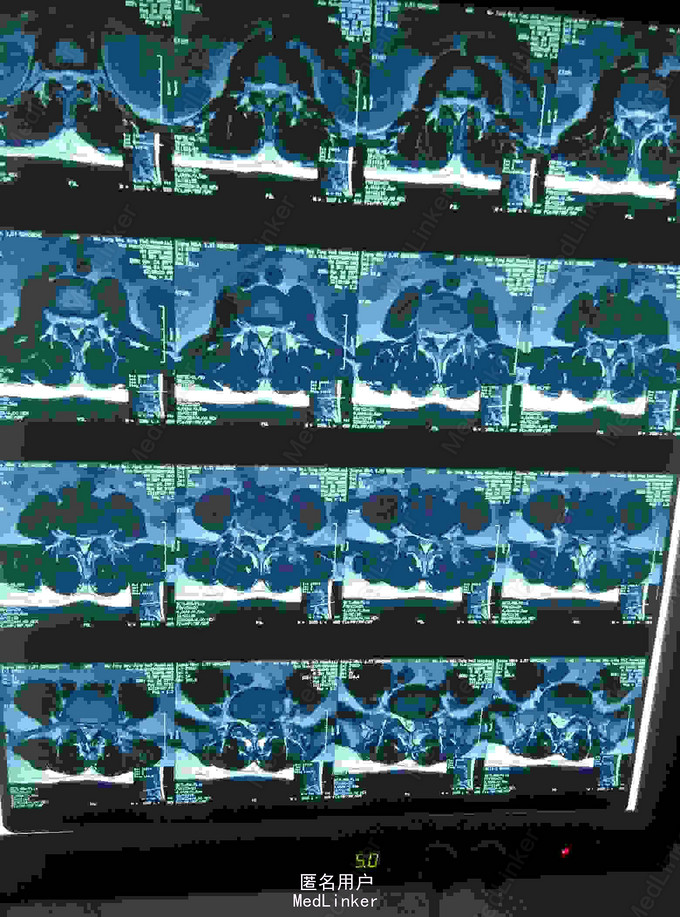

腰椎间盘突出

腰痛伴左下肢疼痛麻木3年

椎间盘突出穿破后后纵韧带游离到硬膜囊背侧

腰椎间盘突出,腰椎间孔镜治疗